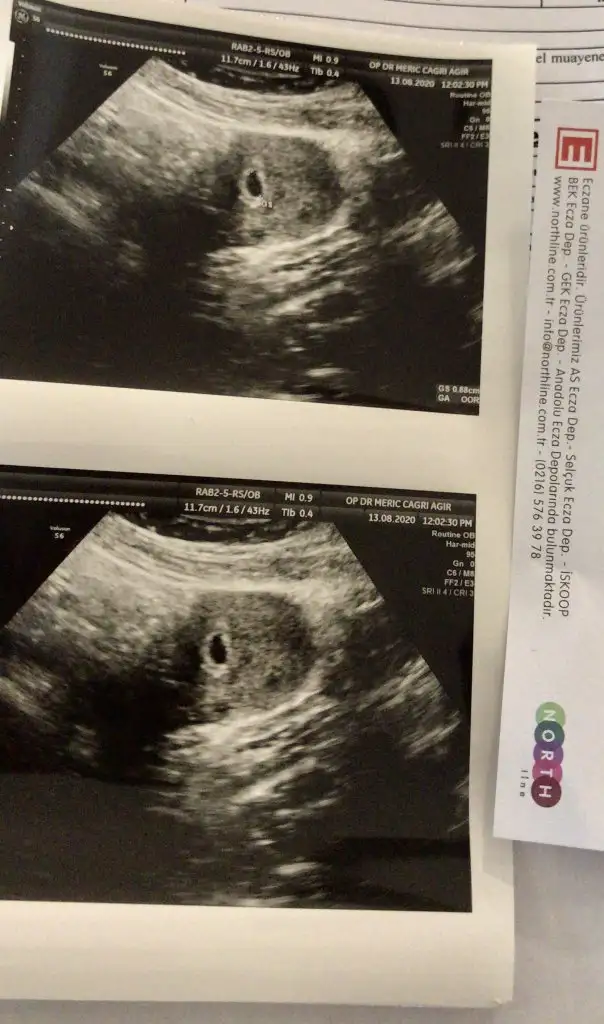

Kızlar bende doktordan geldim şimdi çok şükür keseyi gördük biraz zorlandık çünkü doktor rahmin sola dönmüş dedi böyle bir bilginiz var mı ya ilişkiye kesinlikle girmeyin dedi bir hafta sonra tekrar kontrol edecek zaten tüp bebek olduğu için 2 aydır yasak 🤣🤣🤣

Ultrasonumda böyle kızlar içini dolu gibi görüyorum dedi doktor tabi ama ben birşey göremiyorum ☺️

Bende görmedim ama kendisi yakınlaştırıO baktı içi boş değil haftaya daha net görünür dedi